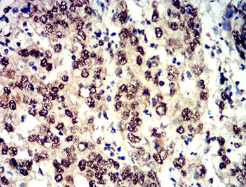

Phospho-4E-BP1 (Ser65) Mouse Monoclonal antibody[2D1G1]

AC3165 Phospho-4E-BP1 (Ser65) Mouse Monoclonal antibody[2D1G1] 100ug $367 10days

Immunogen:    Synthesized peptide of human Phospho-4E-BP1 (Ser65).

FCM    1/200 - 1/400